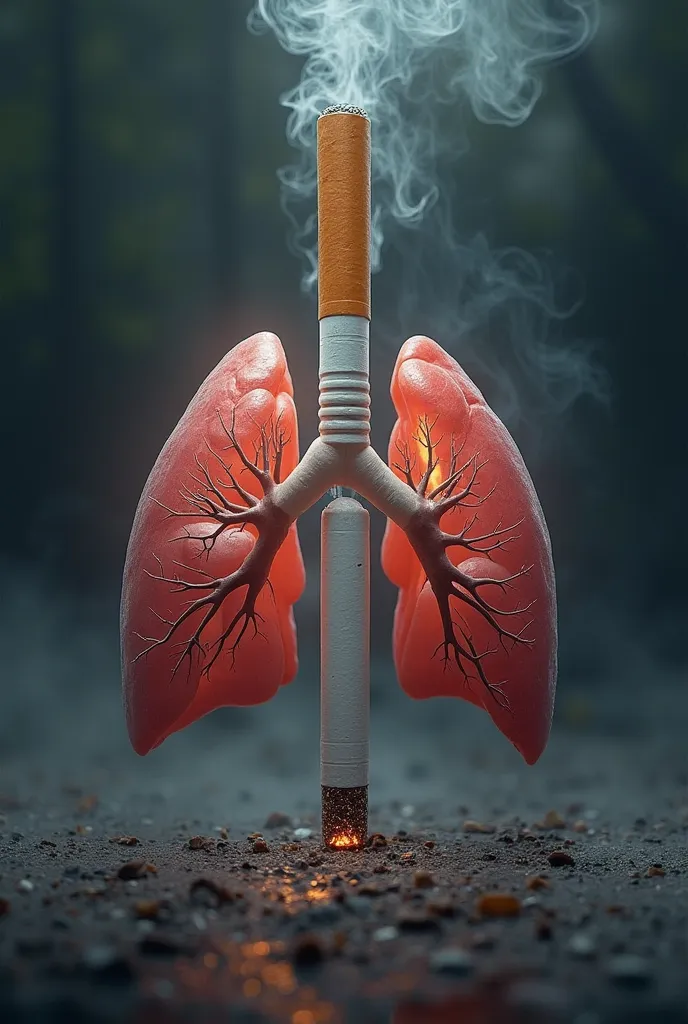

Generate a lungs, the right side lungs is healthy vibrant color surrounded with

Generate a lungs, the right side lungs is healthy vibrant color surrounded with fresh air. On the left side make the lungs damage or pollution of elements in smoking. Add some symbols of no smoking in the pulution part, and add some clean air in the right side lungs

Generate a lungs

the right side lungs is healthy vibrant color surrounded with fresh air

On the left side make the lungs damage or pollution of elements in smoking

Add some symbols of no smoking in the pulution part

and add some clean air in the right side lungs